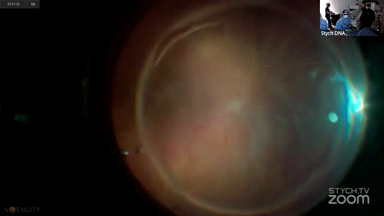

Viewer Discretion Advised: The videos may contain graphic images of surgical procedures that could be disturbing. Viewer discretion is advised. The site is intended for users who are 18 years or older, and no viewers under 18 years of age are allowed unless the use of the site is part of a class within an institution of secondary education and the viewing is supervised by an adult education professional.